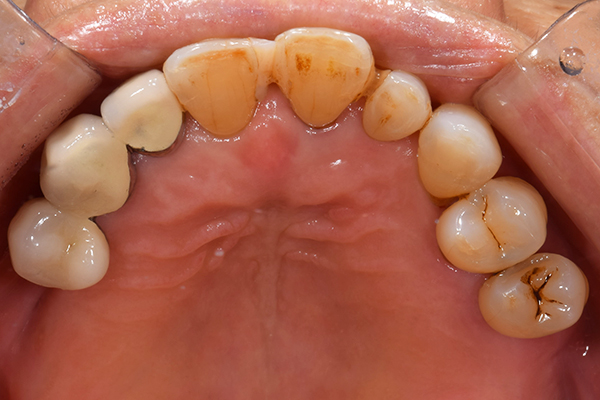

ケース3(インプラントを用いた部分入れ歯)

右上と左下の歯がない方です。 上の入れ歯の安定が悪く、作り直したいとのことでいらっしゃいました。 今お使いの上の入れ歯を見てみると、口蓋部分が抜けており、安定性に欠ける構造になっていました。この入れ歯はノンメタルクラスプデンチャーといって、金属のバネを使用しない 入れ歯になります。これは見た目は良いのですが、歯への負担が大きいことと、入れ歯自体がやわらかいため、噛むには不便なことがあります。

入れ歯は極力薄くするために金属を使用しました。しっかり噛める様にするため、ノンメタルクラスプデンチャーにはしませんでした。

上の入れ歯(表)

上の入れ歯(裏)

下の入れ歯

入れ歯を入れた状態のお口の中の写真です。バネも極力目立たないように作成しています。

年齢 70代・女性

主訴 上の入れ歯の安定が悪く、作り直したい

治療期間 5ヶ月

治療費 .診査診断:55,000円

.インプラント埋入:165,000円

.アバットメント:33,000円

.義歯:330,000円

治療方針 右片側のみ奥歯がない方です。

この様な場合入れ歯は反対側に維持を求めるため、大きな入れ歯になりがちです。

そのため違和感が強いことがおおいです。

また、片側だけないですので、安定もむずかしくなります。

そこで、安定をよくするために、右の奥歯の位置にインプラントをいれて、義歯が揺れない様にすることにしました。

治療内容 レントゲンをみて最低限の長さのインプラントを右上の奥歯の位置に埋入しました。インプラントと骨の結合(オッセオインテグレーション)と歯肉の治癒を待ち、アバットメントをいれて型取りをして、入れ歯を作成しました。極力薄くするために、金属をもちいた入れ歯にしました。

特記事項 インプラントは必ず成功するというものではありません。 また治癒も人それぞれで、長くかかることもあります。 入れ歯を入れ終わったあとも、アバットメントが緩んできたり、入れ歯が歯ぐきにあたって痛いところもでてきますので、調整は必要になります。